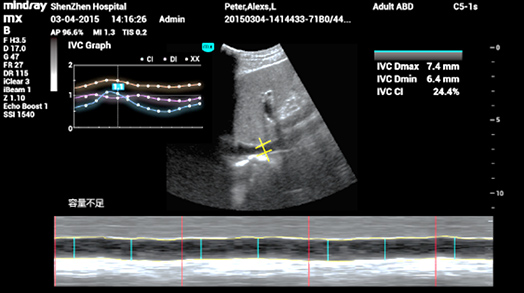

3Smart IVC

Automatic measurement of IVC (Inferior Vena Cava) parameters, helps for volume status assessment and guides the fluid therapy. A graph of parameters change about CI or DI and IVCV for monitoring the change of critical ill patients.